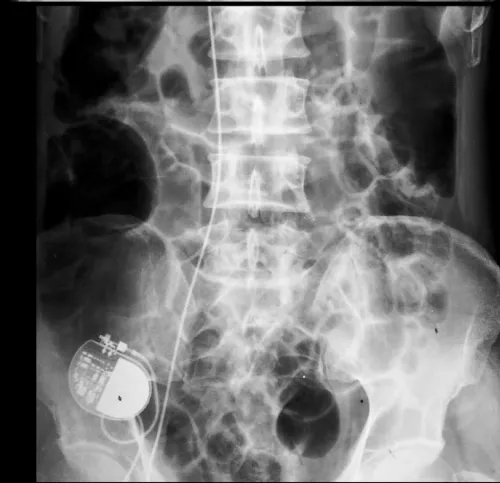

Due to exhaustion of other options, alternative access option was warranted. Therefore, pacemaker implantation via right external iliac vein (EIV) was considered. Under aseptic conditions and local anesthesia, a guidewire was placed in right common iliac vein by puncturing right femoral vein. With fluoroscopic guidance, right EIV was punctured 4 cm above midpoint of inguinal ligament after making an incision and dissecting upto fascial plane, with a 16-gauge needle taking care to avoid arterial puncture (Figure 2). Using a 16 cm peel away sheath, a long RV active fixation lead (Lead 5076, 85 cm, Medtronic) was screwed in RV apex after satisfactory pacemaker parameters were achieved. An alpha loop was made in right atrium to reduce risk of dislodgement (Figure 3). An inverted L-shaped dissection was done around puncture site and lead was doubly secured to external oblique fascia, at the puncture point, and, after making a U-turn superiorly using an additional suture sleeve (Figure 2, schematic). Lead was then tunneled subcutaneouly to the pacemaker pocket created by a separate incision over right lumbar region above external oblique fascia. A VVIR (RESR01-RELIA, Medtronic) pulse generator was also doubly secured to underlying fascia and subcutaneous tissue to prevent gravitational sagging. Finally, tissue and skin were sutured in layers and pressure dressing was done. Operating time was 78 minutes. Abdomino-thoracic radiograph showing final position of old leads and new implant is seen in figure 4.

Figure 3: (Final position of pacemaker, new transiliac ventricular lead (#), old subclavian atrial (@) & ventricular leads (@), and epicardial lead (*) on thoracic-abdominal radiograph.

Figure 4: Abdomino-thoracic radiograph showing final position of old leads and new implant.